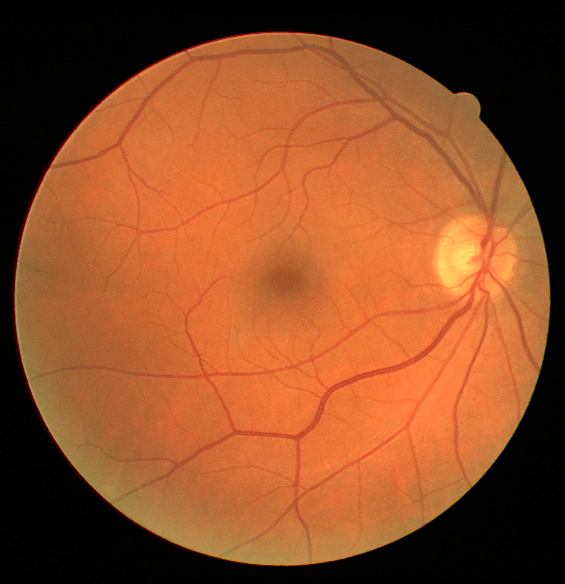

III The RAVIR Dataset

Recently there has been a substantial increase in the utilization of single wavelength confocal imaging that only captures reflected light passing through a pinhole, which will allow capturing high quality, high contrast fundus images. The images in our RAVIR dataset were captured using infrared (815nm) Scanning Laser Ophthalmoscopy (SLO), which in addition to having higher quality and contrast, is more convenient for the patient and is less affected by opacities in optical media and pupil size. This imaging modality is also commonly used in ophthalmology clinics. The RAVIR dataset consists of 46 IR retinal images from the UCLA Stein Eye Institute imaging database, divided into train and test sets of 26 and 20 images, respectively. We used 4 images from the 26 test images as our validation set. The images were captured using a Heidelberg Spectralis camera with a FOV. They are sized at pixels and compressed in the Portable Network Graphics (PNG) format. Each pixel in the images has a reference length of 12.5 microns. Table I compares our RAVIR dataset against other retinal vessel segmentation datasets.

As described in Table III, a wide variety of retinal pathologies are covered by the dataset. These conditions may all affect the retinal vascular pattern and infrared retinal background. For example, diabetic retinopathy and vein occlusions may cause vascular caliber changes and signal blocking from retinal hemorrhage or edema. Peripapillary atrophy causes increased infrared reflectance around the Optic Nerve Head (ONH). Hypertensive retinopathy can manifest as vessel narrowing and arteriovenous nicking, which is the segmental narrowing of veins at arterial crossing points. Severe myopia can cause increased signal transmission of choroidal vessels.

Manual pixel-wise annotations were performed and verified by our experienced retinal image analysis specialist. Per-pixel labels were applied to all vessel regions that could accurately be identified as artery or vein. Vessels were labeled over the ONH in those images where the arteries and veins could be resolved. However, for images in which the veins and arteries over the ONH were indistinguishable, the ONH region was blocked for masking.